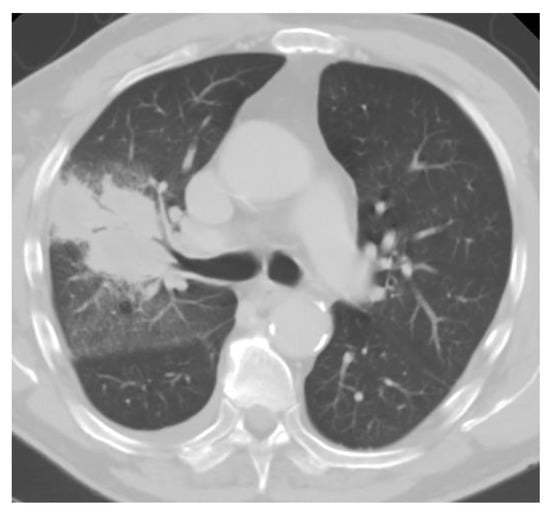

Chest imaging typically reveals diffuse patchy opacities or interstitial infiltrates, which can be associated with hilar and mediastinal adenopathy (Figure 4). Tree-in-bud opacities are less common. Nodules eventually calcify and are the most common finding from prior exposures [52]. Some individuals may develop large nodules, consolidations, acute respiratory distress syndrome, and progressive disseminated histoplasmosis. Of note, patients with disseminated disease often have normal chest imaging [29,53].

Figure 4.

Chest CT of acute pulmonary histoplasmosis showing a large consolidation with air bronchogram.